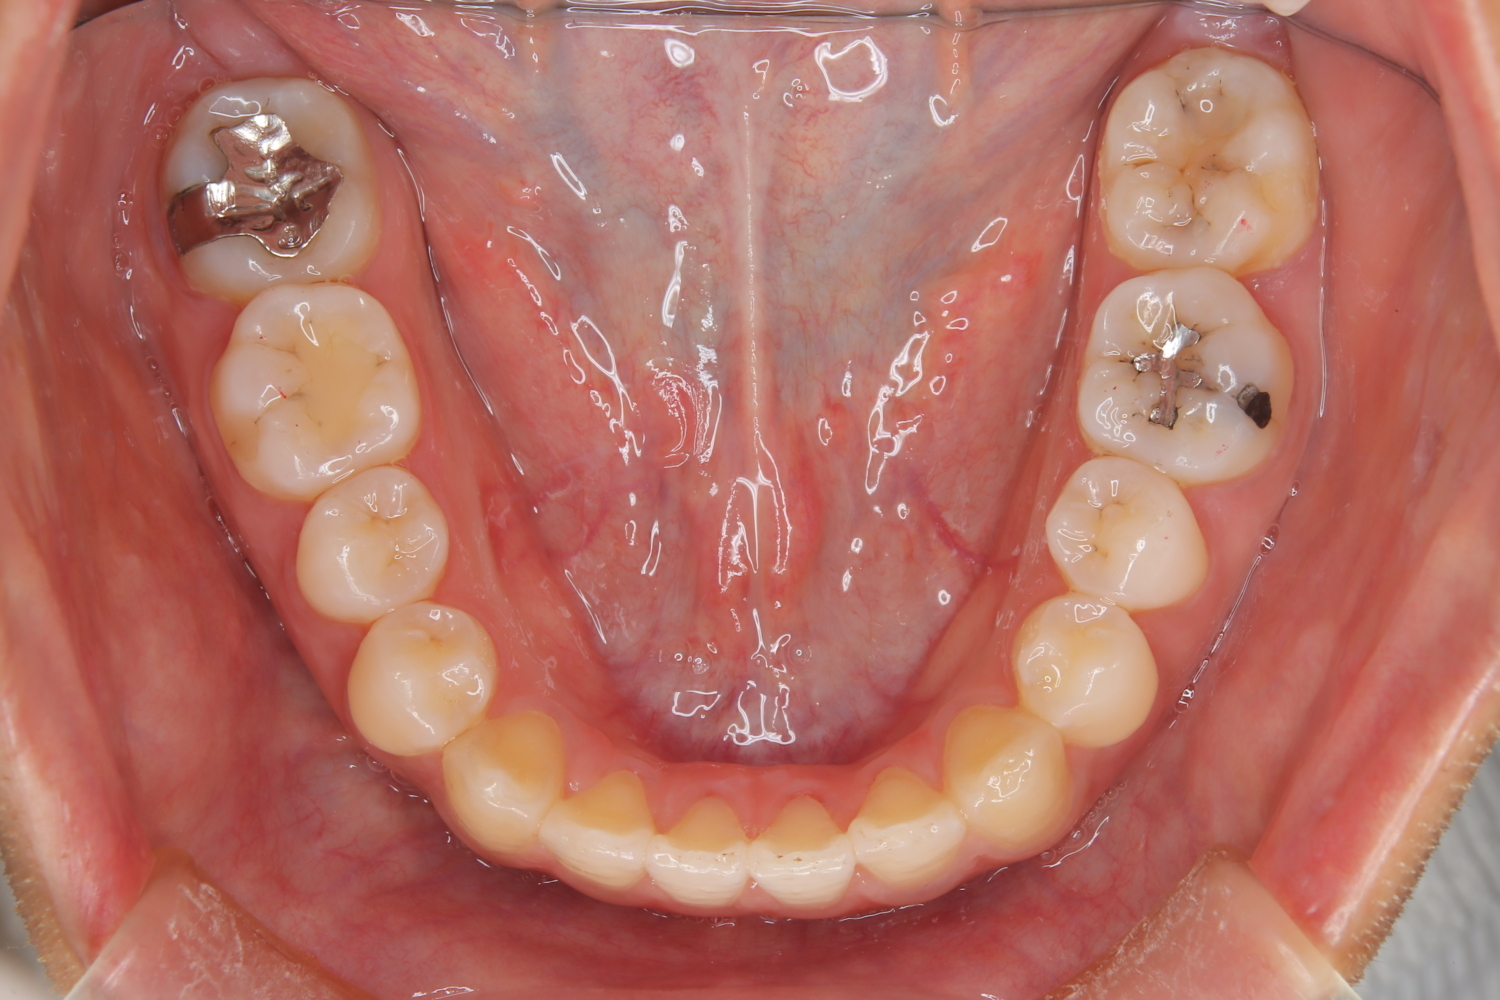

受け口の改善を主訴にご来院された患者様です。

軽度の下顎前突と診断し、マウスピース矯正装置(インビザライン)を用いて治療を行うこととしました。

治療の際はゴム掛けが必要になりましたが、患者様が非常に真面目に使用してくださったおかげで、スムーズに治療が進みました。途中の海外赴任という大きな予定変更がありましたが、そのご努力の甲斐あって、無事に渡航前に矯正を完了することができました。